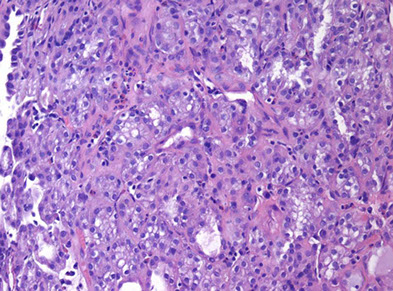

Intraductal carcinoma c dense cribriforming pattern

Same case as left image, showing patchy intact basal layer (p63)

Intraductal Carcinoma of the Prostate (IDC-P)

Intraductal spread of a malignant prostatic AC

- frequently assoc c aggressive and high Gleason score invasive acinar adenocarcinoma

- is a prolif of pleomorphoic malignant cells (with nuclear sizes up to 6x nuclear sizes in adjacent invasive adenocarcinoma)

- expands ductal structures, but has at least a partial / patchy basal cell layer (rules out invasive acinar or ductal AC)

- rarely can be id'd on bx material in absence of infiltrating carcinoma

- vs HG-PIN, has a more dense cribriform pattern with overtly more solid than luminal areas (ie ratio of solid to luminal areas >70%)

- may show small cell-like change

- IDC-P on prostate bx is freq assoc c HG ca and poor px at radical prostatectomy

- thus most likely represents an advanced stage of tumor progression c intraductal spread of tumor in most cases

Infiltrating cribriform acinar AC (Gleason 4 or 5 c comedonecrosis) closely mimics cribriform IDC-P

- most cases if IDC-P would be dx'd as cribriform ca if IHC demonstrating basal cells had not been performed

- in some cases, contour and branching pattern of normal duct architecture suggests the dx of IDC-P as opposed to infiltrating ca

- the tx of IDC-P and infiltrating HG-prostate AC are the same, so distinction not critical on bx

- purely IDC-P at radical prostatectomy is 100% cured by surgery, the same may not be true of an infiltrating ca

- if there is no definitive infiltrating ca on H&E sections and a suggestion of IDC-P in a core, then basal stains are recommended to differentiate IDC-P from infiltrating carcinoma

Intraductal carcinoma of the prostate with PIN4 cocktail highlighting basal cells